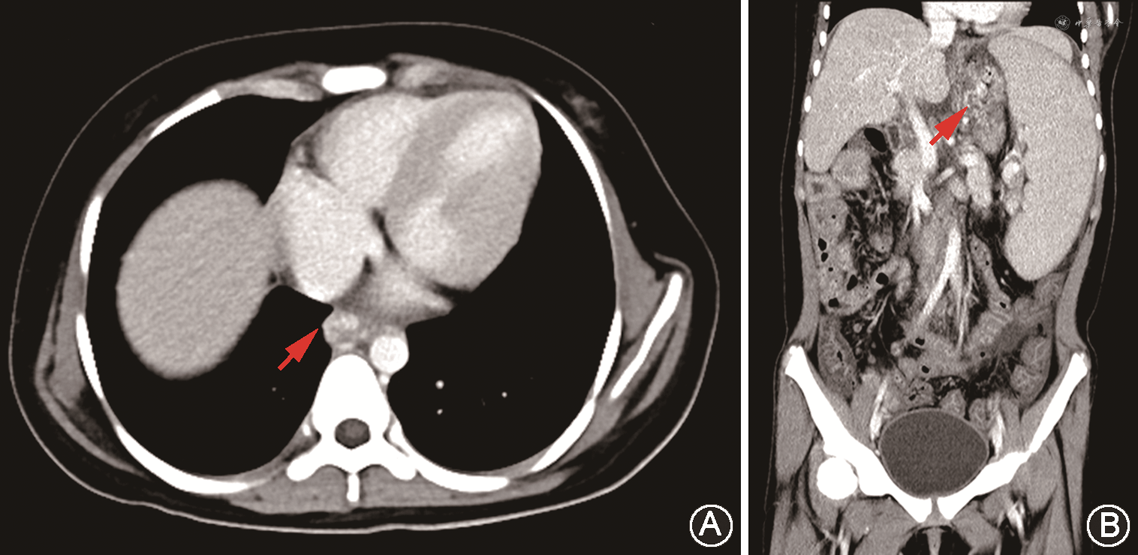

14个月后该患儿因“呕血伴黑便10余天”再次入院。急查血常规:血红蛋白53 g/L,血小板108×109/L。糖化血红蛋白6.78%。末梢血糖波动于5.6~15.0 mmol/L。肝功能:总胆红素90.1 μmol/L,直接胆红素37.0 μmol/L,间接胆红素53.1 μmol/L,总蛋白54.2 g/L,白蛋白33.5 g/L,丙氨酸转氨酶38 U/L,天冬氨酸转氨酶49 U/L,γ-谷氨酰转肽酶101.3 U/L。超声心动图:全心略大,左心室收缩功能测值正常,肺动脉高压[估测收缩压约40 mmHg(1 mmHg=0.133 kPa)],房水平左向右分流,二、三尖瓣少量反流。腹部彩色超声:肝光点增粗,分布欠均匀;脾大,腹水;食管胃静脉迂曲增宽(内径约2.2 mm)。腹部CT增强扫描:食管胃静脉扩张,肝脏、脾脏增大,腹腔积液,肠壁增厚伴渗出(图4)。该患儿最终诊断为:(1)AS;(2)食管胃静脉曲张出血;(3)重度贫血;(4)智力低下。入院后急予输注红细胞悬液补充血容量、生长抑素降低门静脉压力、奥美拉唑抑酸及药物止血等治疗;并予小剂量呋塞米及螺内酯减轻心脏负荷、卡托普利预防心肌重构。拟于波生坦降低肺动脉高压,但因肝功能异常暂缓口服。患儿此次消化道出血原因考虑为食管胃静脉曲张破裂出血所致,家属要求保守治疗,故未行内镜检查治疗及肝脏穿刺活检。经上述治疗后患儿消化道出血停止,病情好转出院,嘱其密切随访。